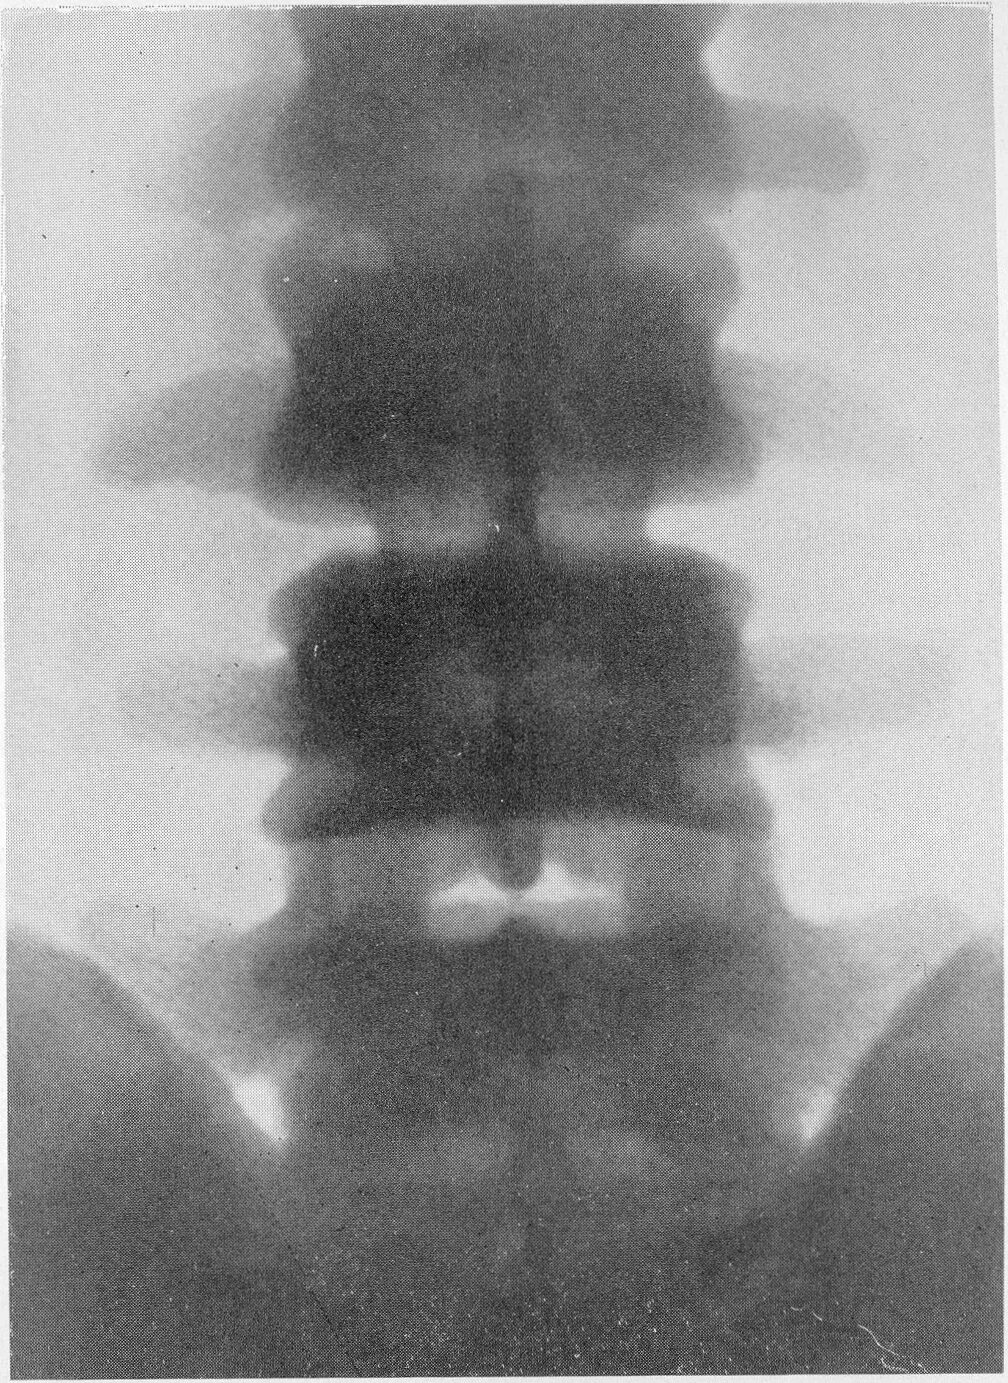

Остеосклероз грудного отдела